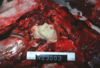

Q

This is a picture of a rumen. What lesion is shown here?

A

Acute, multifocal to coalescing ulcerative ruminitis